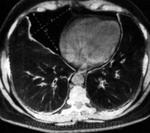

Пациент 75 лет поступил с клинической картиной правосторонеей пневмонии 20.02.12, по поводу чего лечился до 02.03.12 сейчас клиники пневмонии нет и готовят на выписку в удовлетворительном состоянии. А картина на контроле через две недели такая же. Возможно предположить наличие прямых или косвенных признаков центрального Neo правого легкого ?. Заранее спасибо!

ИМХО: справа в S3 было и сохраняется уплотнение лёгочной ткани перибронхиального харктера, которое с учётом клиники, можно раcценить как проявление пневмонии, которая в настоящий момент клинически разрешилась.Только вопрос какого характера пневмония -банальная или вторичная, параканкрозная остаётся открытым.Показана РКТ ( если недоступна, то как суррагат последней  срединная линейная томография, на проходимость бронхов) + бронхоскопия. Я бы ещё постарался поднять ФЛО-архив- не нравится низкое расположение малой междолевой плевры в медиальном отделе, за счёт чего это произошло?- уменьшение в объёме средней доли? ( если-да, то когда это возникло сейчас или давно?) или вздутие S3? Если ничего не сделают и выпишут пациента, то в случае варианта, что пневмония была на фоне нарушения проходимости бронха опухолевого генеза, следут ожидать скорого рецидива пневмонии.

после детальной оценки предоставленной вами рентгенограммы вижу следующие изменения :в S3 верхней доли правого легкого определяется участок гиповентиляции(гипоателектаз) со сближением элементов легочного рисунка(сосудов и бронхов), в проекции  субсегментарной ветви правой легочной артерии  опеределяется участок фиброза(причем рискну сказать,что это не пневмофиброз,а утолщение центрального перибронховаскулярного интерстиция).у меня 2 версии возникновения гипоателектаза S3:первая учитывая фиброз -это фиброателектаз(поствоспалительный большой давности),второй это постстенотический -необходимо исключить центральный рак в S3 суб- или сегментарного бронха!!! с уважением федя

Если посмотреть на боковую R-грамму лёгких от 20.02.12г, то нижние отделы занимает только тень диафрагмы, каких-то дополнительных образований в базальных отделах нет. На боковой R-грамме  от 2.03.12г.определяеся округлая тень( да и не одна), липома  за 10 дней вырасти не могла, скорее это тень нескольких скатов купола диафрагмы. Собственно говоря, сам факт наличия или отсутствия липомы не актуален, для пацента в 75 лет т.к. если она даже есть, это никак не моменяет тактику ведения пациента. Принципиальное значение имеет вопрос, что происходит с лёгкими и какой ожидать прогноз.